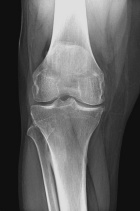

51 year old male with six month history of knee pain, worse after MVC

Zoom image: Radiological image Radiological image.